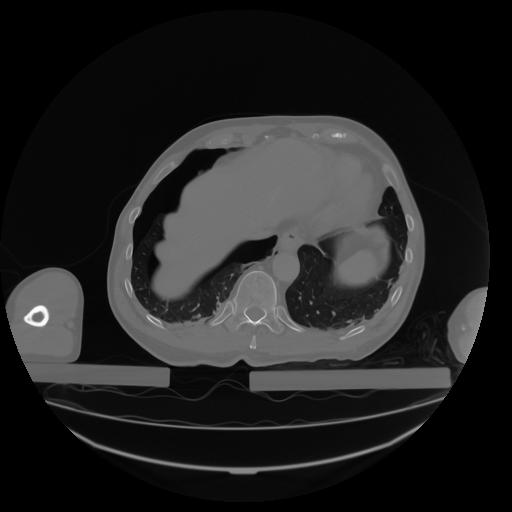

27 CUERPO,CE,Axial,3.0,CUERPO,,